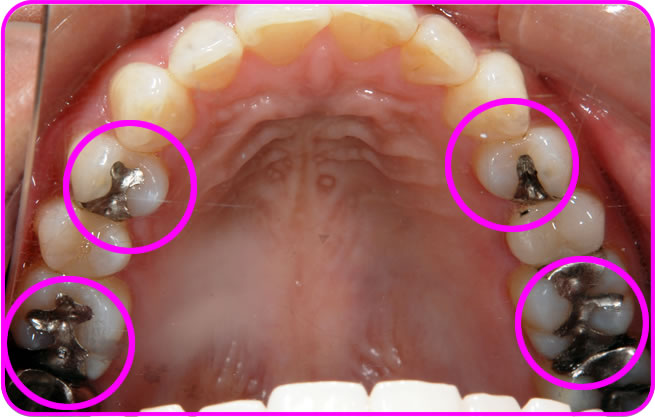

上顎の原因金属

上顎の原因金属を除去後